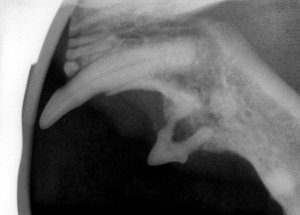

X-ray of a cat with a tooth undergoing tooth resorption. This is a painful condition in which the body attacks normal tooth and bone, leaving compromised teeth. This tooth required extraction due to the advanced nature of this condition.Tooth resorption always needs immediate treatment because it is so painful.